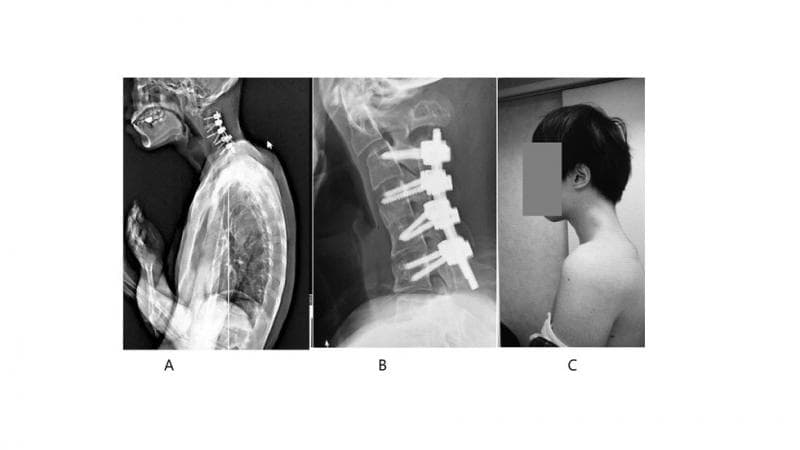

Sejumlah pengobatan akhirnya dilakukan untuk menyembuhkan masalah kesehatan ini. Setelah pemasangan penyangga leher gagal mengembalikan bentuk lehernya seperti semula, operasi pun dilakukan untuk mengangkat sebagian kecil tulang belakang dan jaringan parut yang nggak normal, serta memasang batang logam serta sekrup untuk menopang leher.

Pada akhirnya, sekitar enam bulan setelah operasi tersebut berhasil dilakukan, sang laki-laki kembali bisa menegakkan kepalanya. Sekitar setahun kemudian,dia sudah bisa menelan makanan dengan normal.